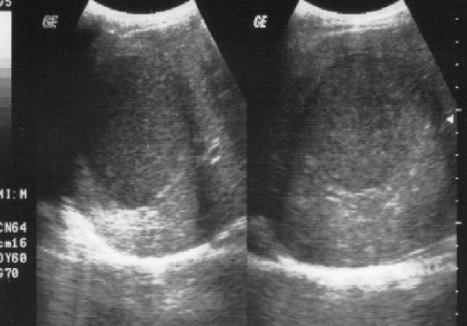

Image aechogen a

multilobulaire , abord fine du foie gauche en aspect de grappe "

cluster sign " d'une abces du foie en susgeste

une abces a pyogenes |